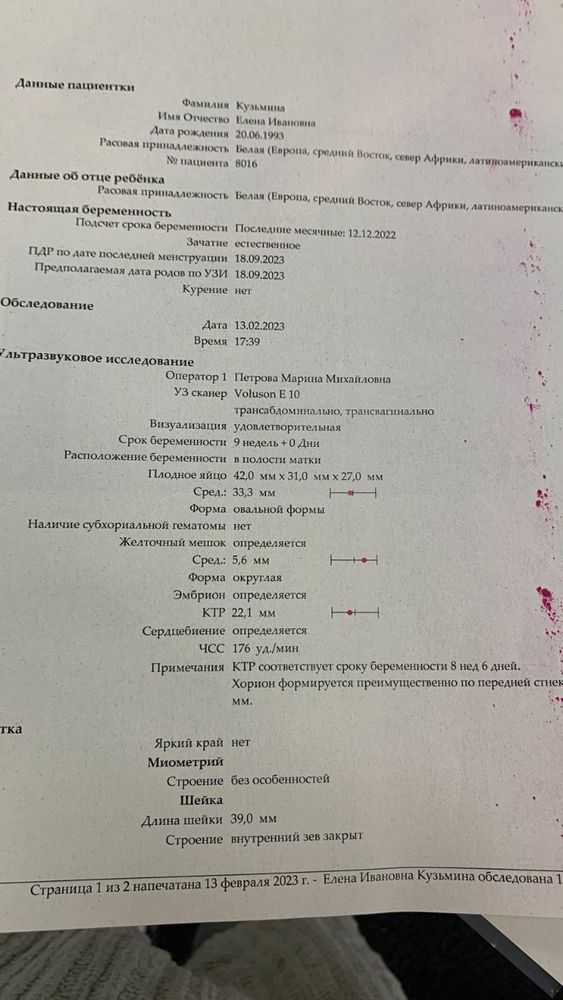

Вот есть ещё узи от 13 февраля

Вот есть ещё узи от 13 февраля

Марина, то было 13 февраля, а это 15 марта